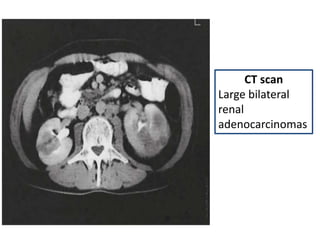

CT scan

Large bilateral

renal

adenocarcinomas